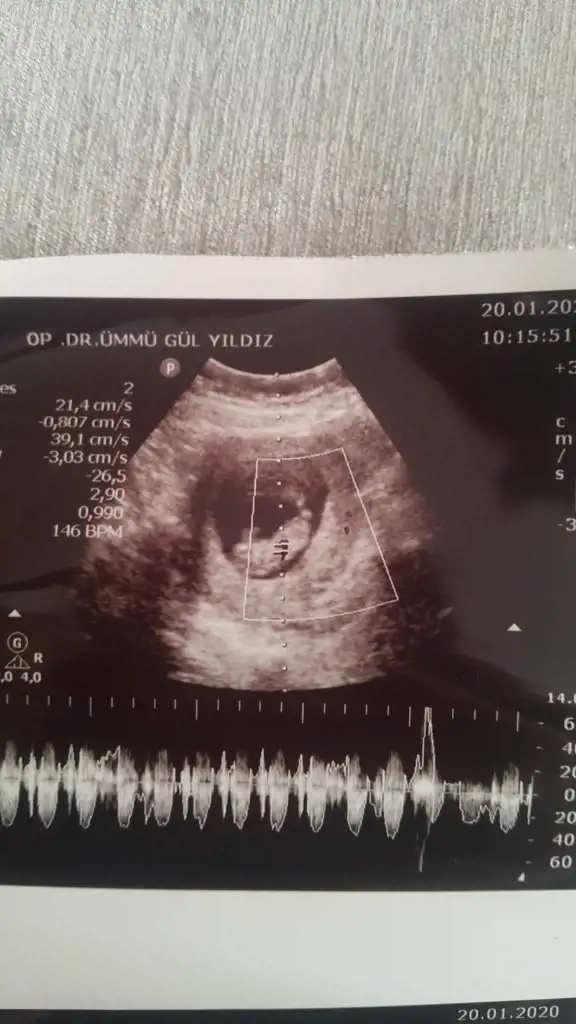

Screenshot_20200120-154357.webp

mrhaba lütfen yorumlarmisiniz sizce kızmı erkekmi bi arkadas icin soruyorum